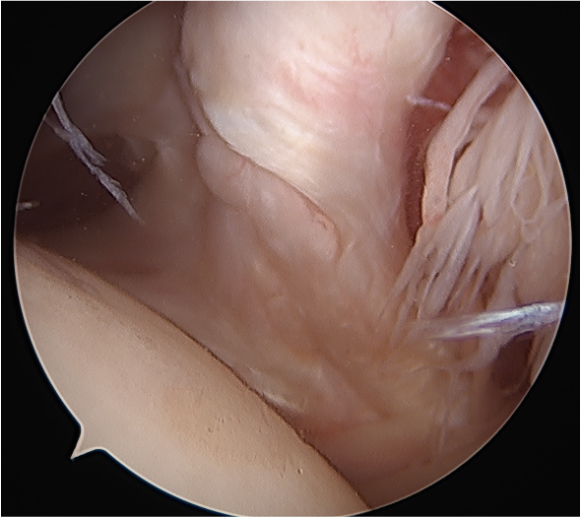

Full thickness retracted subscapularis tear with comma sign

Full thickness completely retracted subscapularis, loss of rotator interval and comma sign